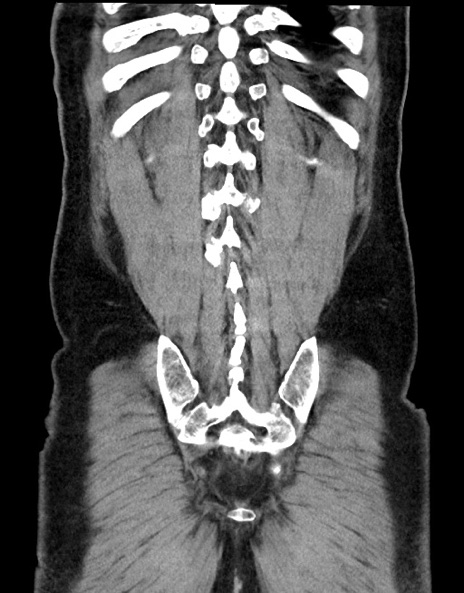

症例15(冠状断像)

【症例】70歳代男性

【主訴】腹痛

【現病歴】今朝から腹痛あり。全体的に痛い。特に左上の方。排ガスが今日はない。冷や汗が出る。

【既往歴】直腸癌術後

【身体所見】左側腹部〜上腹部に圧痛あり。腹膜刺激症状明らかなではない。軽度反跳痛。左下腹部に術後瘢痕あり。

【データ】WBC 7700、CRP 0.02